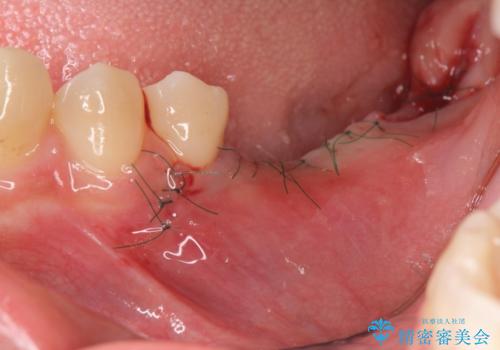

放置したことによる影響か骨が吸収し、インプラント周囲に十分な骨が確保できないような状況であったため骨造成を併用したインプラント治療を計画します。

- 外科手術のため、術後に痛みや腫れ、違和感を伴います